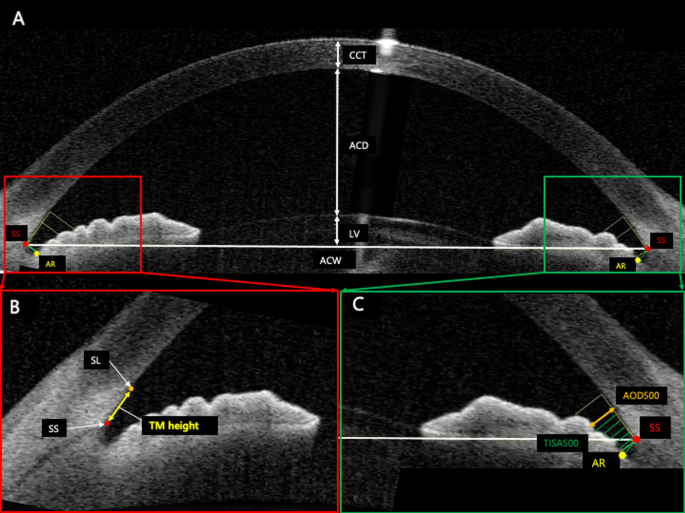

For TM height measurement, we used the standard protocol, the SL method; Crowell et al. and Seager et al. noted that SL is a hypo-reflective structure that reflects the starting point of TM and termination point of corneal endothelium and identifies the inner apex of the U-shaped interface via BELL (Fig. 1)29. Therefore, the TM height of enrolled eyes was analyzed with the two important landmarks, SS and SL.

Measurement of TM height and ocular parameters using anterior segment optical coherence tomography (AS-OCT). The overall anterior segment OCT endpoints (A). The measurement of the TM height defined as the distance between scleral spur (SS) and Schwalbe’s line (SL) (B). Anterior angle parameters of AOD 500 and TISA 500. SS scleral spur, AR angle recess, CCT central cornea thickness, ACD anterior chamber depth, LV lens vault, ACW anterior chamber width, SL Schwalbe’s line, TM trabecular meshwork, AOD angle opening distance, TISA trabecular iris space area.

A range of ocular parameters (e.g., angle, anterior chamber, lens, and corneal parameters) measured from both the temporal and nasal sides using AS-OCT were as follows: anterior chamber depth (ACD) (i.e., defined as the distance between the corneal endothelium and the anterior capsule of the lens), anterior chamber width (ACW) (i.e., the distance between the two SS), angle opening distance (AOD) (i.e., the perpendicular distance between the TM), angle recess area (ARA) (i.e., the triangular area bounded by AOD as the base, angle recess as the apex), and the inner corneoscleral wall as the sides of triangle), trabecular iris space area (TISA) (i.e., the trapezoidal area with the boundaries of anterior for the AOD), trabecular iris angle (TIA) (i.e., the angle measured with the apex in the iris recess), lens vault (LV) (i.e., the perpendicular distance between the anterior lens pole and the horizontal line joining the two SS). The central corneal thickness (CCT) of all the patients was also assessed from cross-sectional AS-OCT images by manually computing the width of the cornea. In addition to these parameters, ocular assessments including current and past ophthalmologic diagnosis and baseline IOP measurements were obtained from the evaluated medical records. Finally, IOL Master (Carl Zeiss Meditec AG, Jena, Germany) was used to measure the AXL.